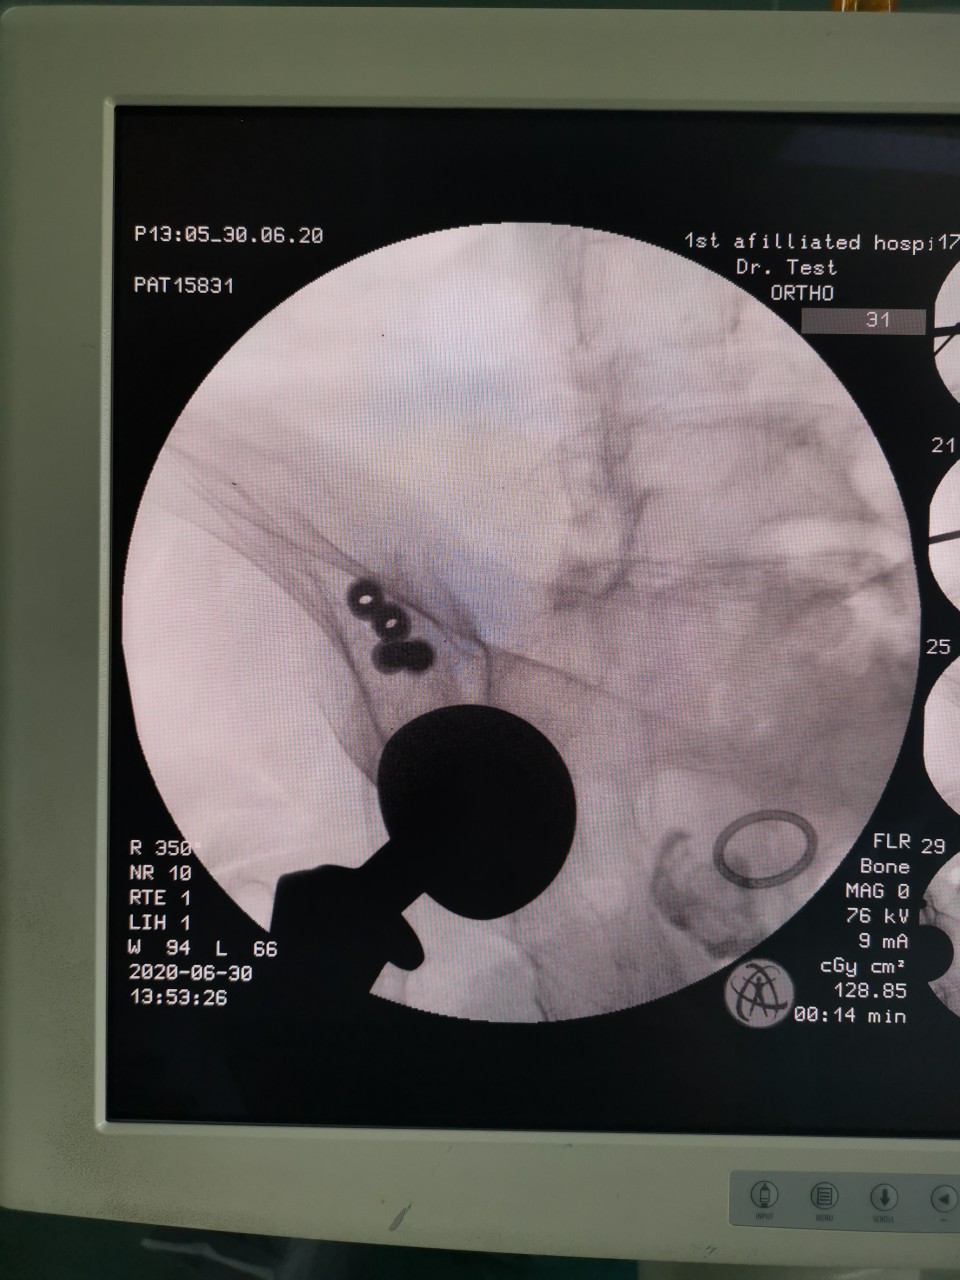

术中复位

患者女,81岁,既往曾因股骨颈骨折行右髋关节置换术,此次入院当天因外伤致髋部周围疼痛及活动受限入住我院创伤骨科。经术前检查及评估,诊断为“骨盆骨折”。对于此例高龄骨盆骨折患者,王刚副主任医师团队决定为其施行“闭合复位微创内固定手术”,手术用时仅30分钟,在闭合复位后,通过3枚骨盆通道螺钉固定骨折部位,基本无手术出血,术后两天患者恢复良好,予以出院。